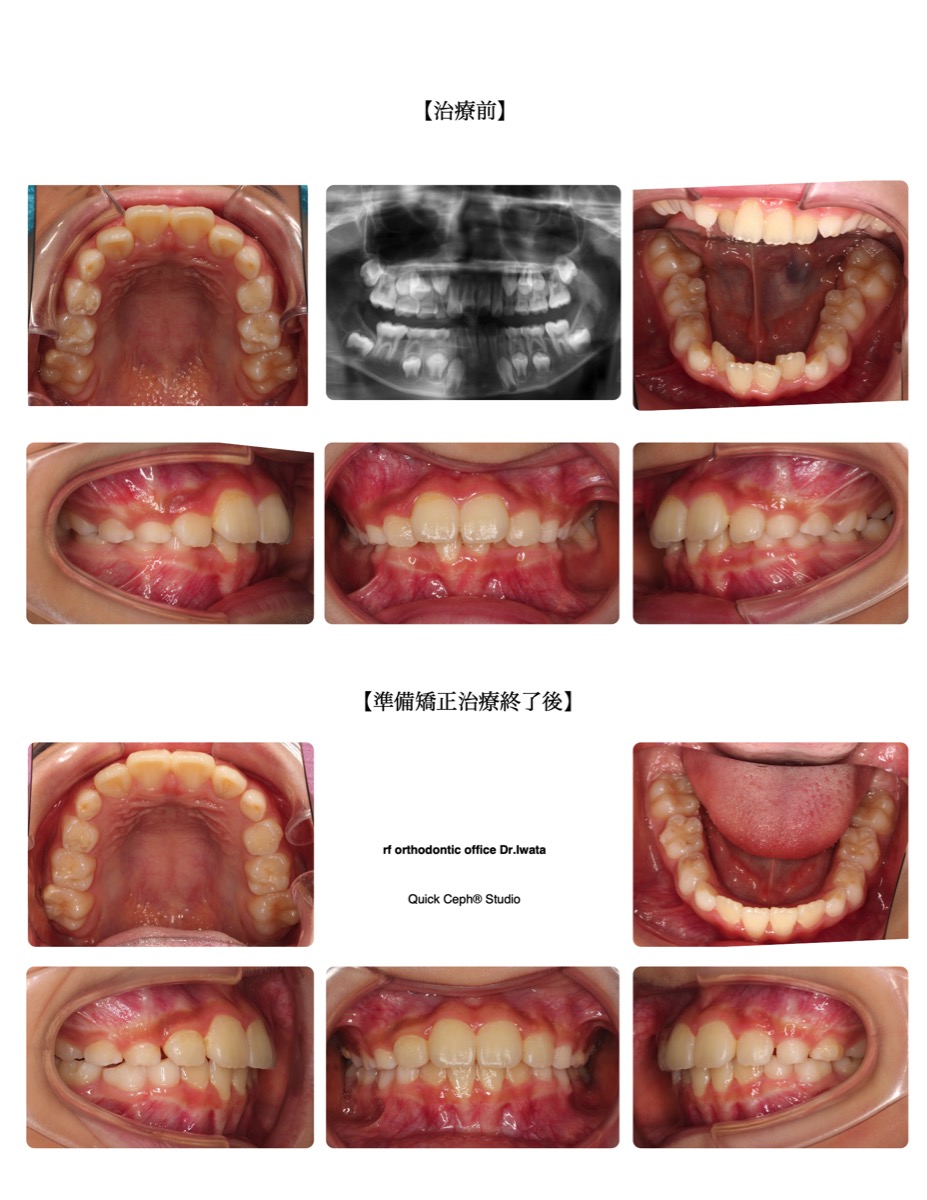

【主訴】上下の前歯がガタガタに生えてきた。特に上の前歯がハの字になってきて今後の歯並びが心配。【主な症状】叢…